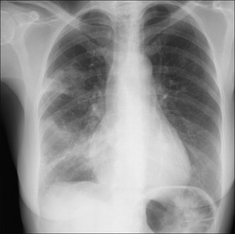

image

Figure 28.1 Chronic dyspnoea. Extensive alveolar shadowing. Wide differential diagnosis. Apply Golden Rule 1—clinical details are crucial. Known renal failure with fluid retention. CXR conclusion—alveolar pulmonary oedema.